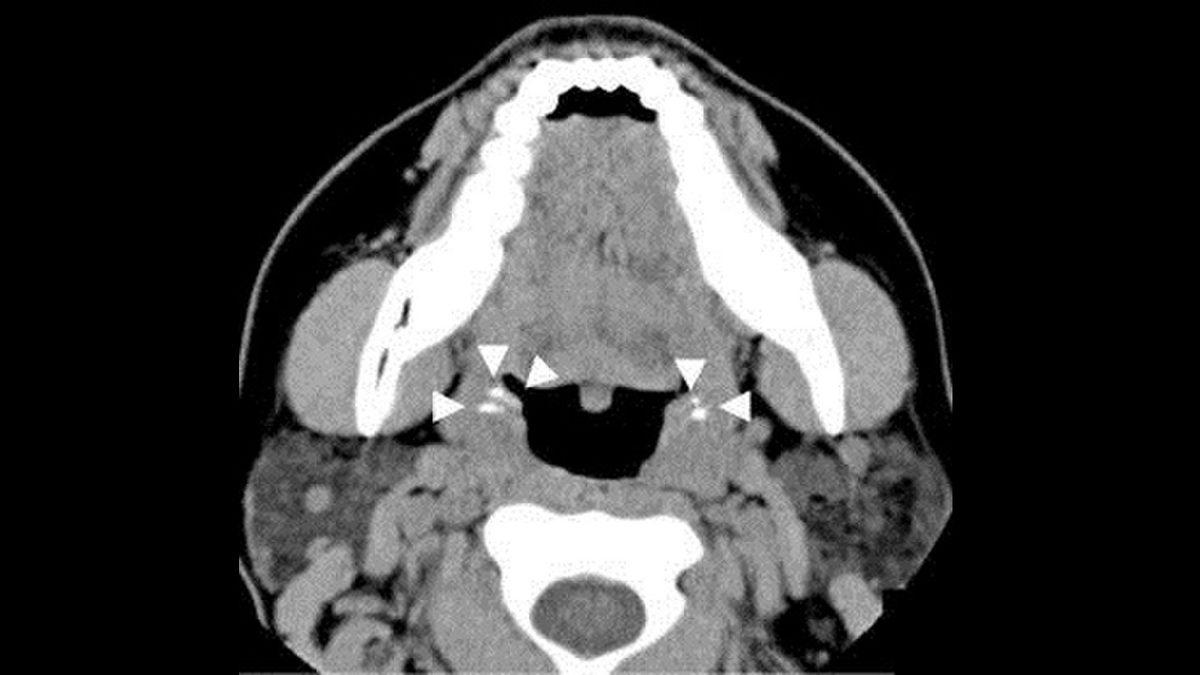

Boğazımızın hemen gerisinde bez benzeri iki adet bademcik adı verilen yapı bulunur. Bu yapının temel amacı ağız yoluyla vücudumuza giren bakteri ve mikrop gibi yabancı maddeleri engellemektir. Bazen bademciklerde mukus, bakteri, besin artığı ve benzeri biriktiği zaman bademcik taşı adı verilen bir rahatsızlık meydana gelir. Bademcik taşları küçük çıkıntılardır.